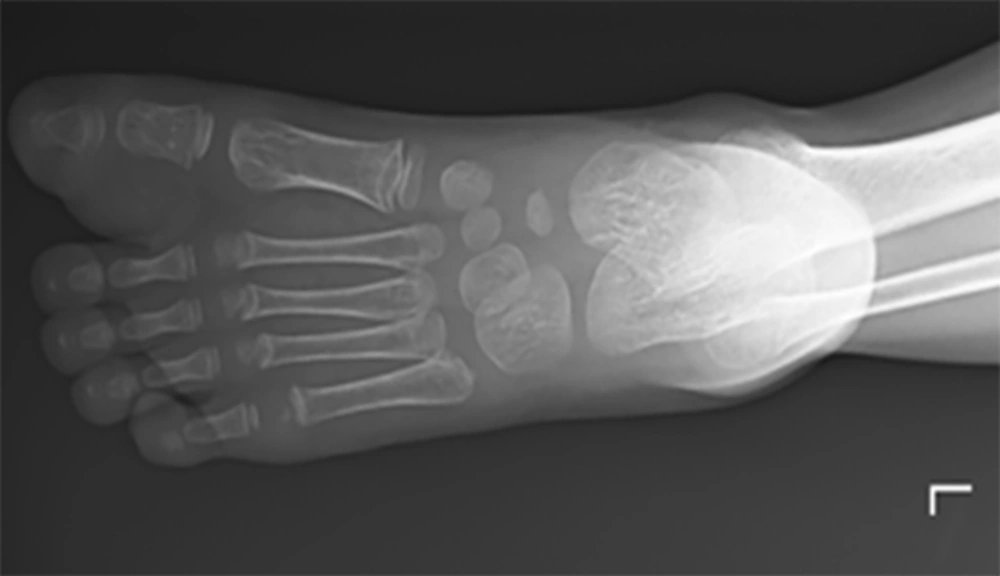

A plain X-ray of the left foot was done to determine if there was bony involvement, and it revealed a soft tissue swelling of the left big toe, as shown in Figure 1 below, causing widening of the first web-space. The adjacent bones appeared normal. Fine needle aspiration was also done from the mass, showing bland spindle cells in a myxoid matrix admixed with adipocytes, which was suggestive of myxolipoma, and excisional biopsy was recommended for confirmation.